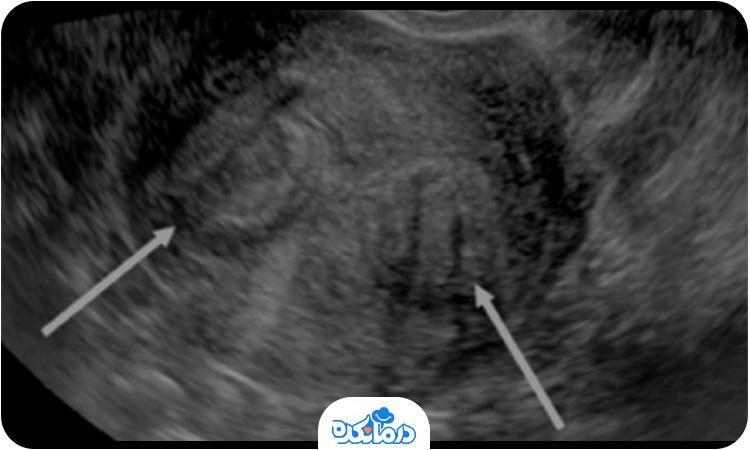

برای تشخیص بیماری حتما باید به پزشک مراجعه کنید. دقت کنید که معاینه، بررسی وضعیت بیمار، اندازه و شکل رحم همگی بخشی از فرآیند تشخیص هستند. از شایعترین روشهای تشخیص این بیماری میتوانیم به سونوگرافی، هیستروسکوپی، لاپاراسکوپی و امآرآی لگن اشاره کنیم. همچنین در صورت نیاز پزشک از سونوگرافی ترانسواژینال هم کمک میگیرد.